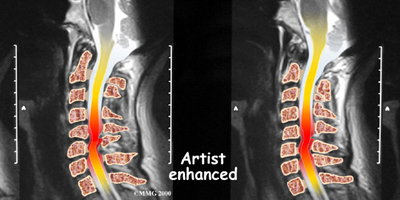

If more information is needed, your doctor may order an MRI. The MRI machine uses magnetic waves rather than x-rays to create pictures of the cervical spine in slices. MRIs show the cervical spine vertebrae, as well as the soft tissue structures, such as the discs, joints, and nerves. MRI scans are painless and don't require needles or dye. MRI scan has become the most common test to look at the cervical spine after x-rays have been taken.

Example of DMX diagnostic video fluoroscopy.